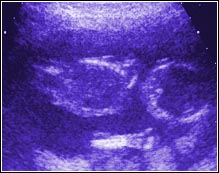

Week Sixteen. The fetus is now six inches long. During

this examination we saw the two hemispheres of a brain,

delicate ears barely protruding from the sides of a head,

a spinal cord like two winding rows of kernels on an ear of corn, and,

as can be seen in this picture, the individual bones of a hand.